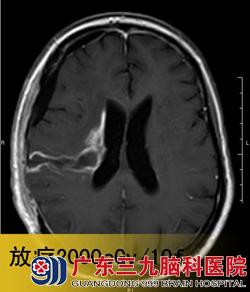

入院见潘女士呈嗜睡状,不能言语,四肢乏力。头颅磁共振检查见右基底节占位性病变,初步考虑为淋巴瘤。www.999brain.com